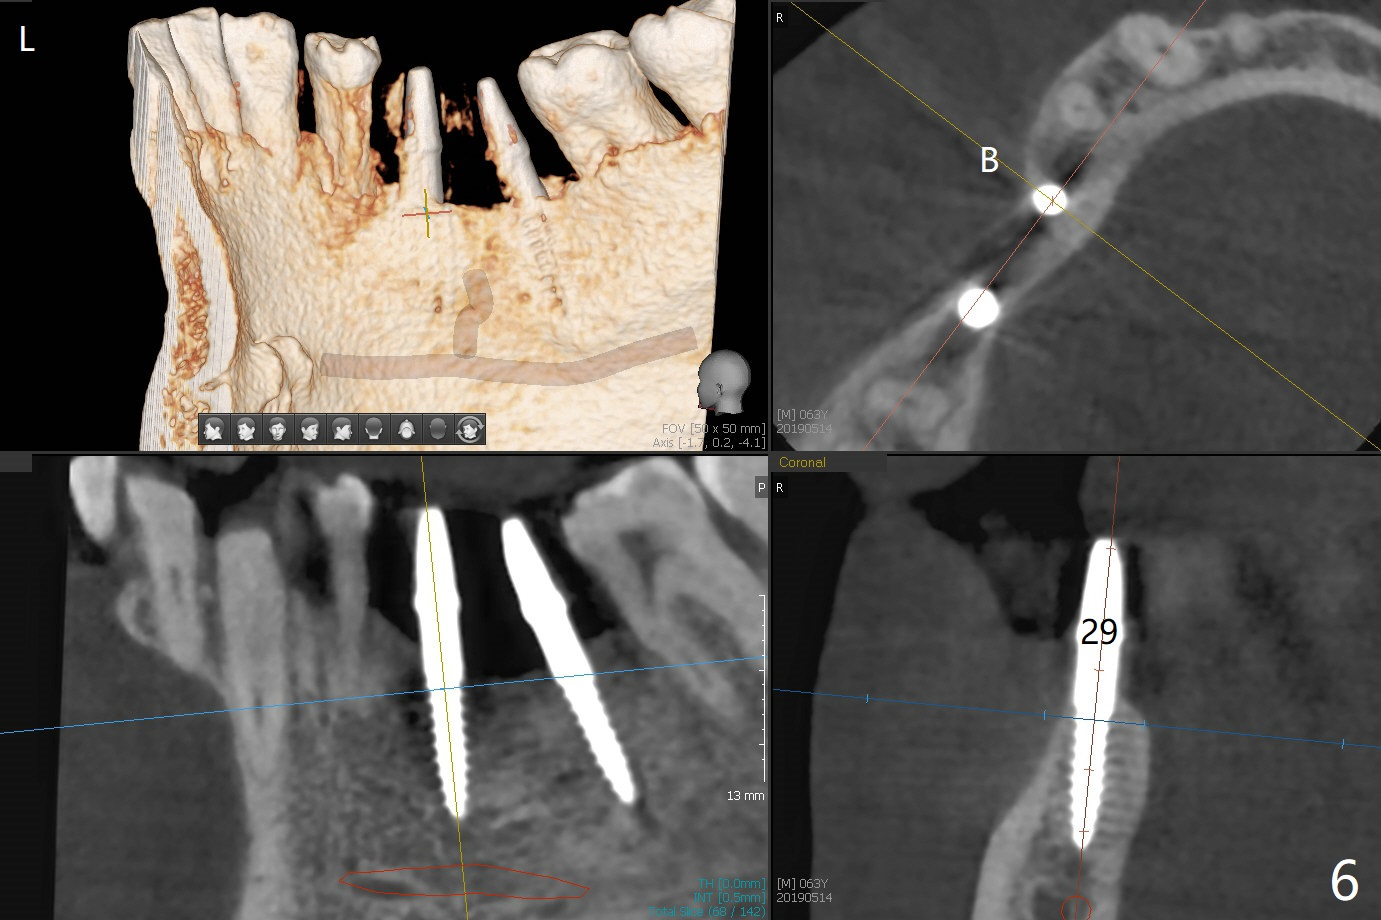

After initial osteotomy using 2.2 mm drill for 10 and 11.5 mm at #29 and 30, respectively, the guide is removed for re-insertion of drills and PA (Fig.1). The osteotomy at #29 is found lingually and in the nonkeratinized gingiva with mild laceration (wish incision to be made before osteotomy); the osteotomy is established a little lingual at #29 (Fig.2) and more or less in the middle of the narrow ridge and #30 (Fig.3). Lindamann bur is used to move #29 osteotomy buccally. A 1.5 mm drill is used to increase the depth free hand before placement of 2.5x10(4) mm 1-piece implants (Fig.4). After adjustment of the implant depth (Fig.5), CT is retaken, which shows proper implant placement (Fig.6,7). Probably due to good oral hygiene, the gingiva around the implants appears to be keratinized 4 months postop (Fig.8). After abutment preparation for margin and parallelism, impression is taken (Fig.9). When the permanent crowns are temporarily cemented, the large gingival embrasure is noted (Fig.10,11). The latter could be reduced by modifying the provisional in the healing stage. In fact the crown at #29 dislodges 2 days post cementation because lingual (Fig.12) and distal (Fig.13) placement. A surgical stent should have been fabricated from RPD for free hand placement!